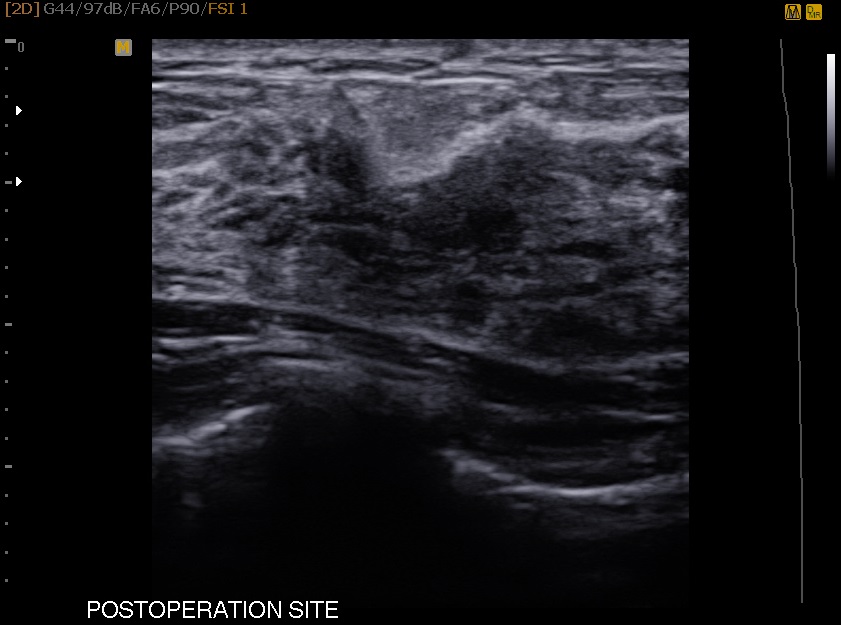

32¼¼ ¿©¼ºÀ¸·Î Áõ»ó ¾øÀÌ À¯¹æ°ËÁø Â÷ ³»¿øÇÏ¿© ÃÊÀ½ÆÄ»ó ¿ìÃøÀ¯¹æ¿¡ ¸ð¾çÀÌ ÁÁÁö ¾ÊÀº Ȥ ¹ß°ßÇÏ¿© Á¶Á÷°Ë»ç ½ÃÇàÇÏ¿´½À´Ï´Ù. Á¶Á÷°Ë»ç °á°ú ¼¶À¯³¶Á¾¼º Áúȯ°ú ºñÁ¤»ó °ü³»Áõ½ÄÁõ Áø´ÜµÇ¾î ¸¾¸ðÅè¼ö¼ú ½ÃÇàÇß½À´Ï´Ù.